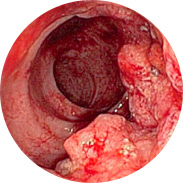

Quali sono i pericoli delleemorroidi negli uomini e nelle donne?

• Infiammazione della mucosa rettale e festering.

• Il sanguinamento può portare all'anemia

• L'aumento della temperatura corporea, con una grave infiammazione, può portare alla febbre.

• E il peggiore di tutti, il cancro al retto!